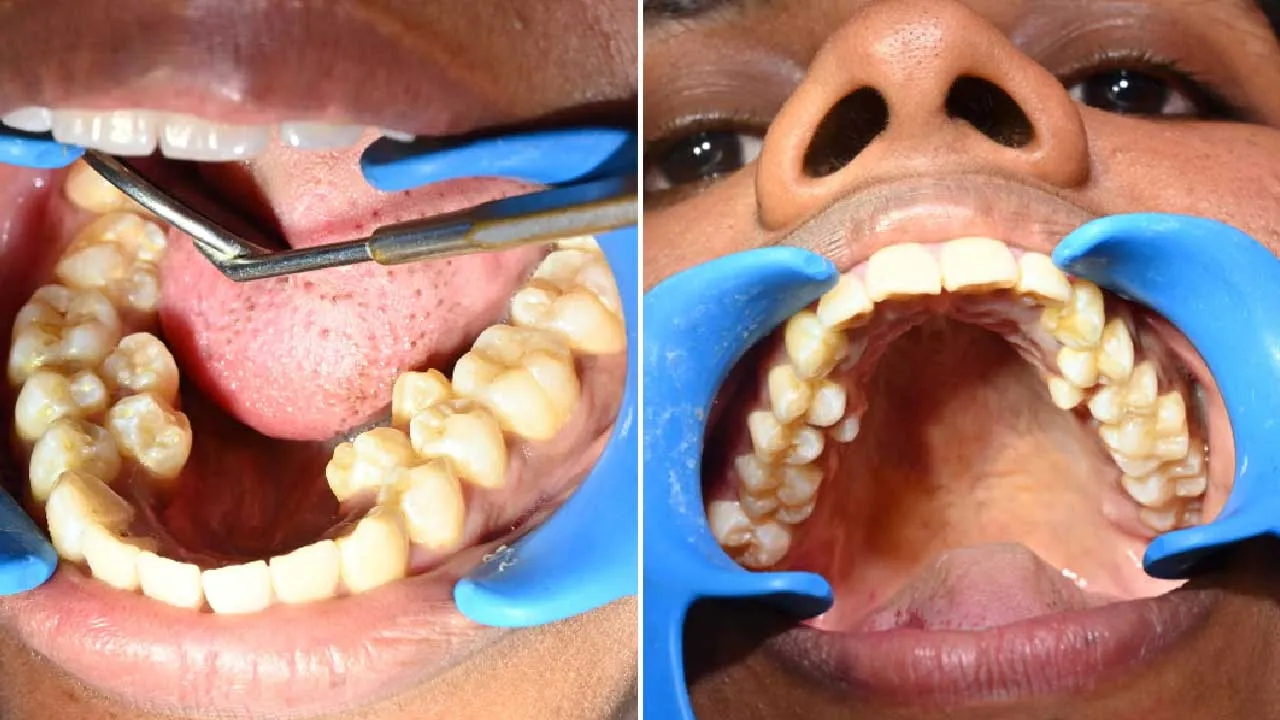

भारत में एक अनोखा विश्व रिकॉर्ड बना है। कल्पना बालन नाम की 26 वर्षीय महिला के मुंह में कुल 38 दांत हैं, जो एक सामान्य व्यक्ति से 6 अधिक हैं। इस उपलब्धि के कारण उनका नाम Guinness World Records में दर्ज किया गया है। ऐसे में सवाल उठता है कि यदि किसी व्यक्ति के मुंह में अतिरिक्त दांत हों, तो क्या उन्हें निकलवा देना चाहिए या रहने देना ठीक है?

सामान्यतः एक वयस्क व्यक्ति के मुंह में 32 दांत होते हैं। लेकिन कल्पना बालन के मुंह में नीचे के जबड़े में 4 और ऊपर के जबड़े में 2 अतिरिक्त दांत हैं। ये दांत किशोरावस्था में धीरे-धीरे उगने लगे थे। उन्हें विशेष दर्द तो नहीं होता, लेकिन खाना खाते समय अक्सर भोजन दांतों के बीच फंस जाता है।